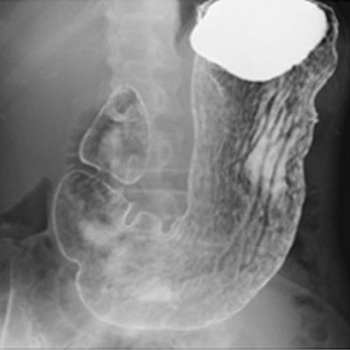

X線透視検査

X線をTVモニターに映像化し、リアルタイムの動画を見ながら検査や治療をおこなっています。バリウム検査や内視鏡検査、骨折整復などで使用しています。